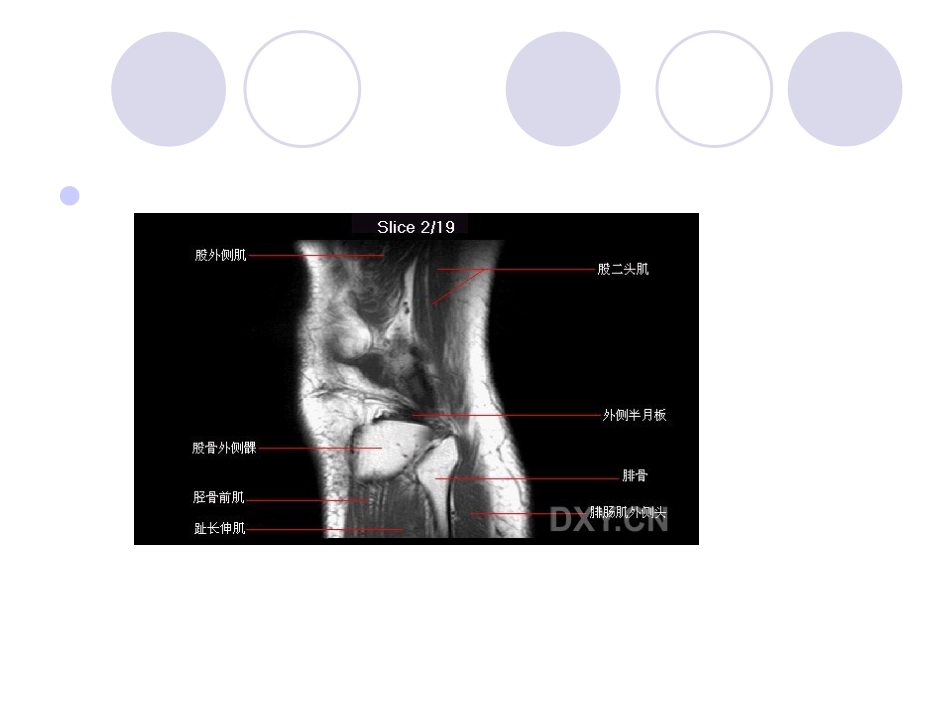

膝关节MRI膝关节MRI诊断之半月板病变半月板损伤是膝关节疼痛的常见原因之一,传统的X线平片及CT扫描不能显示半月板,X线关节造影及CT关节造影虽能显示半月板,但因属于微创伤检查,且CT扫描角度的限制,所以临床上很少应用。磁共振成像因具有高的组织分辨率,可以多方位、任意面成像,是目前检查半月板最好和首选的检查方法。正常半月板在MRI的各个序列中均表现为均匀的低信号影,半月板损伤表现为半月板形态、边缘、大小及其内部信号的改变,按Mink和Fischer提出的方法进行分级1半月板Ⅰ级损伤即早期退变(或变性),在病理上表现为灶性的或早期的半月板粘液样变性,这是由于半月板内纤维软骨基质内的粘多糖产物的增加所致。在MRI的T2WI上表现为半月板内点片状或类圆形高信号影,未达到...